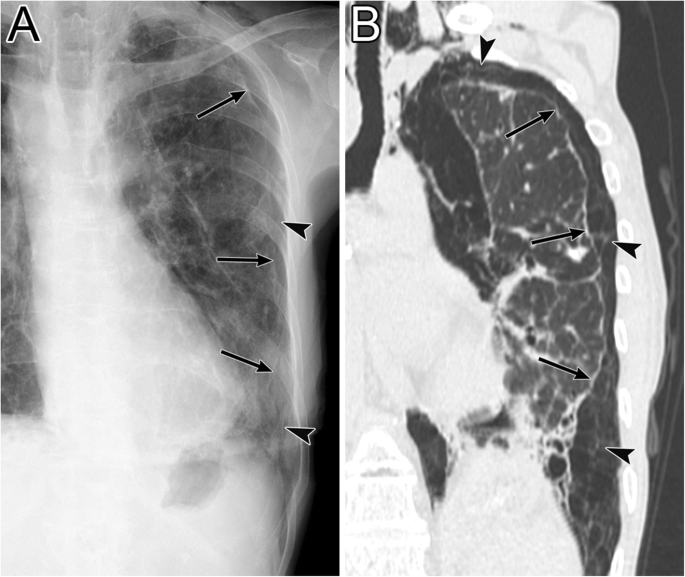

PIE appears radiographically as lucent streaks that radiate from the hila to the periphery of the lung. This finding reflects peribronchovascular air and air within the interlobular septa that resembles an air bronchogram (Fig. 21) [16, 49, 51]. The lucent streaks of PIE tend to be more numerous and more irregular on a radiograph than those of an air bronchogram [49]. Irregular radiolucent mottling in the lung reflects subpleural cysts and parenchymal cysts (Fig. 21) [16, 49, 51]. On a CT image, PIE is visualized as perivascular and peribronchial emphysema, air within the interlobular septa, and subpleural cysts (Fig. 21) [16, 49, 51]. Rapid changes in the distribution and extent of air are characteristic of PIE [36], and it may disappear within 1 to 2 days [49].

Pulmonary interstitial emphysema. a A supine radiograph of a 6-day-old girl with an extremely low birth weight shows generalized irregular radiolucent mottling and perivascular air (black arrow) in the left lung. b An axial chest CT image of a different patient (a 20-month-old girl with pneumonia) shows a subpleural cyst (asterisk), air within the interlobular septa (arrowheads), perivascular and peribronchial emphysema (white arrows), and pneumothorax